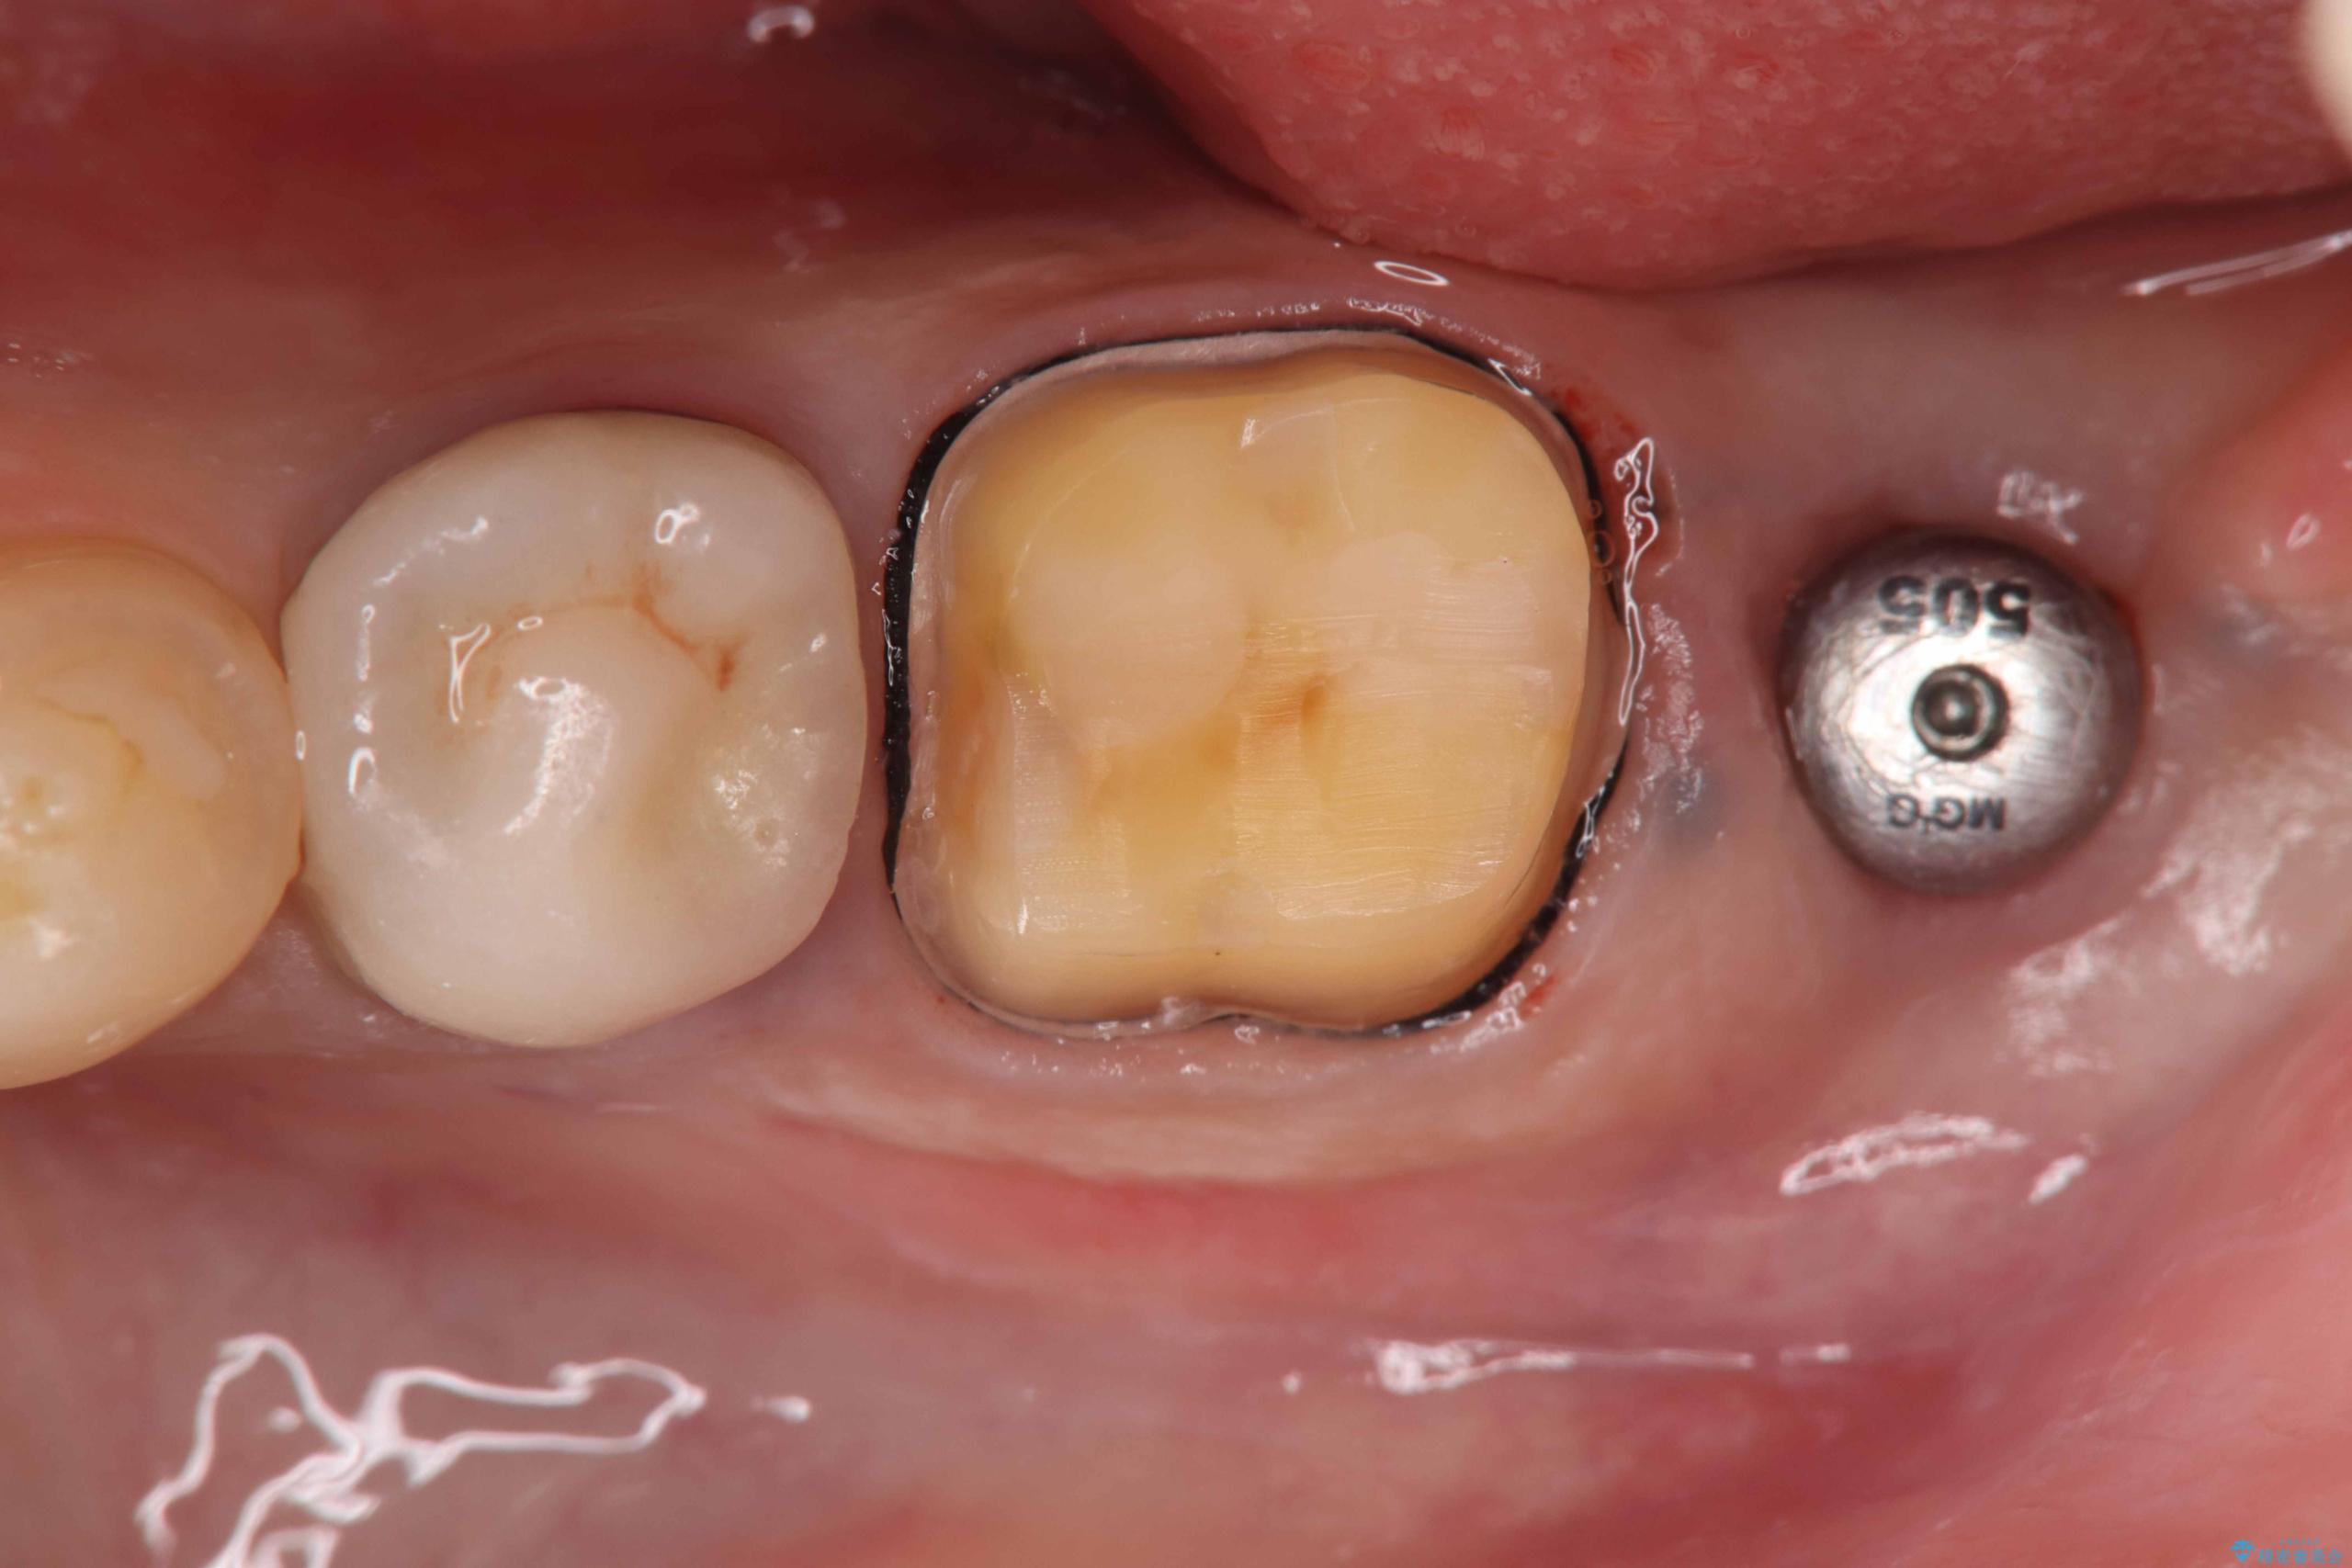

- 過去にヘミセクションが行われていたと思われる左下7番は、大きな歯根嚢胞および根尖病変が認められ、さらに骨縁下カリエスを伴っており、歯肉には瘻孔が形成されている状態でした。

保存は困難と判断し、左下7番は抜歯即時インプラントによる治療を行いました。

また、左下6番には形態が不自然で適合不良のセラミックインレーが装着されていたため、二次カリエスのリスクを考慮し、オールセラミッククラウンによる治療を行いました。